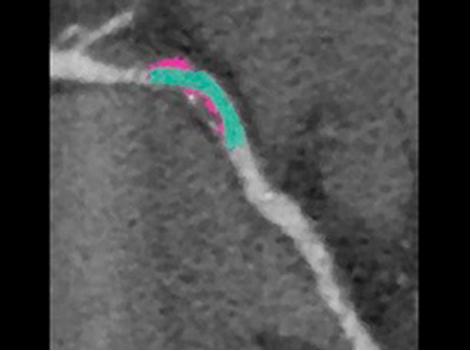

PCI ASSIST13

Help plan, assess and guide interventional procedures with improved visibility up to 85 percent in moving anatomy. Read More

Intervention

Successful PCI of the stenotic lesions involves planning, guidance, and assessment of the culprit lesion and assessment of the remainder of the coronary tree.

PCI ASSIST6

Help plan, assess and guide interventional procedures with improved visibility up to 85 percent in moving anatomy.